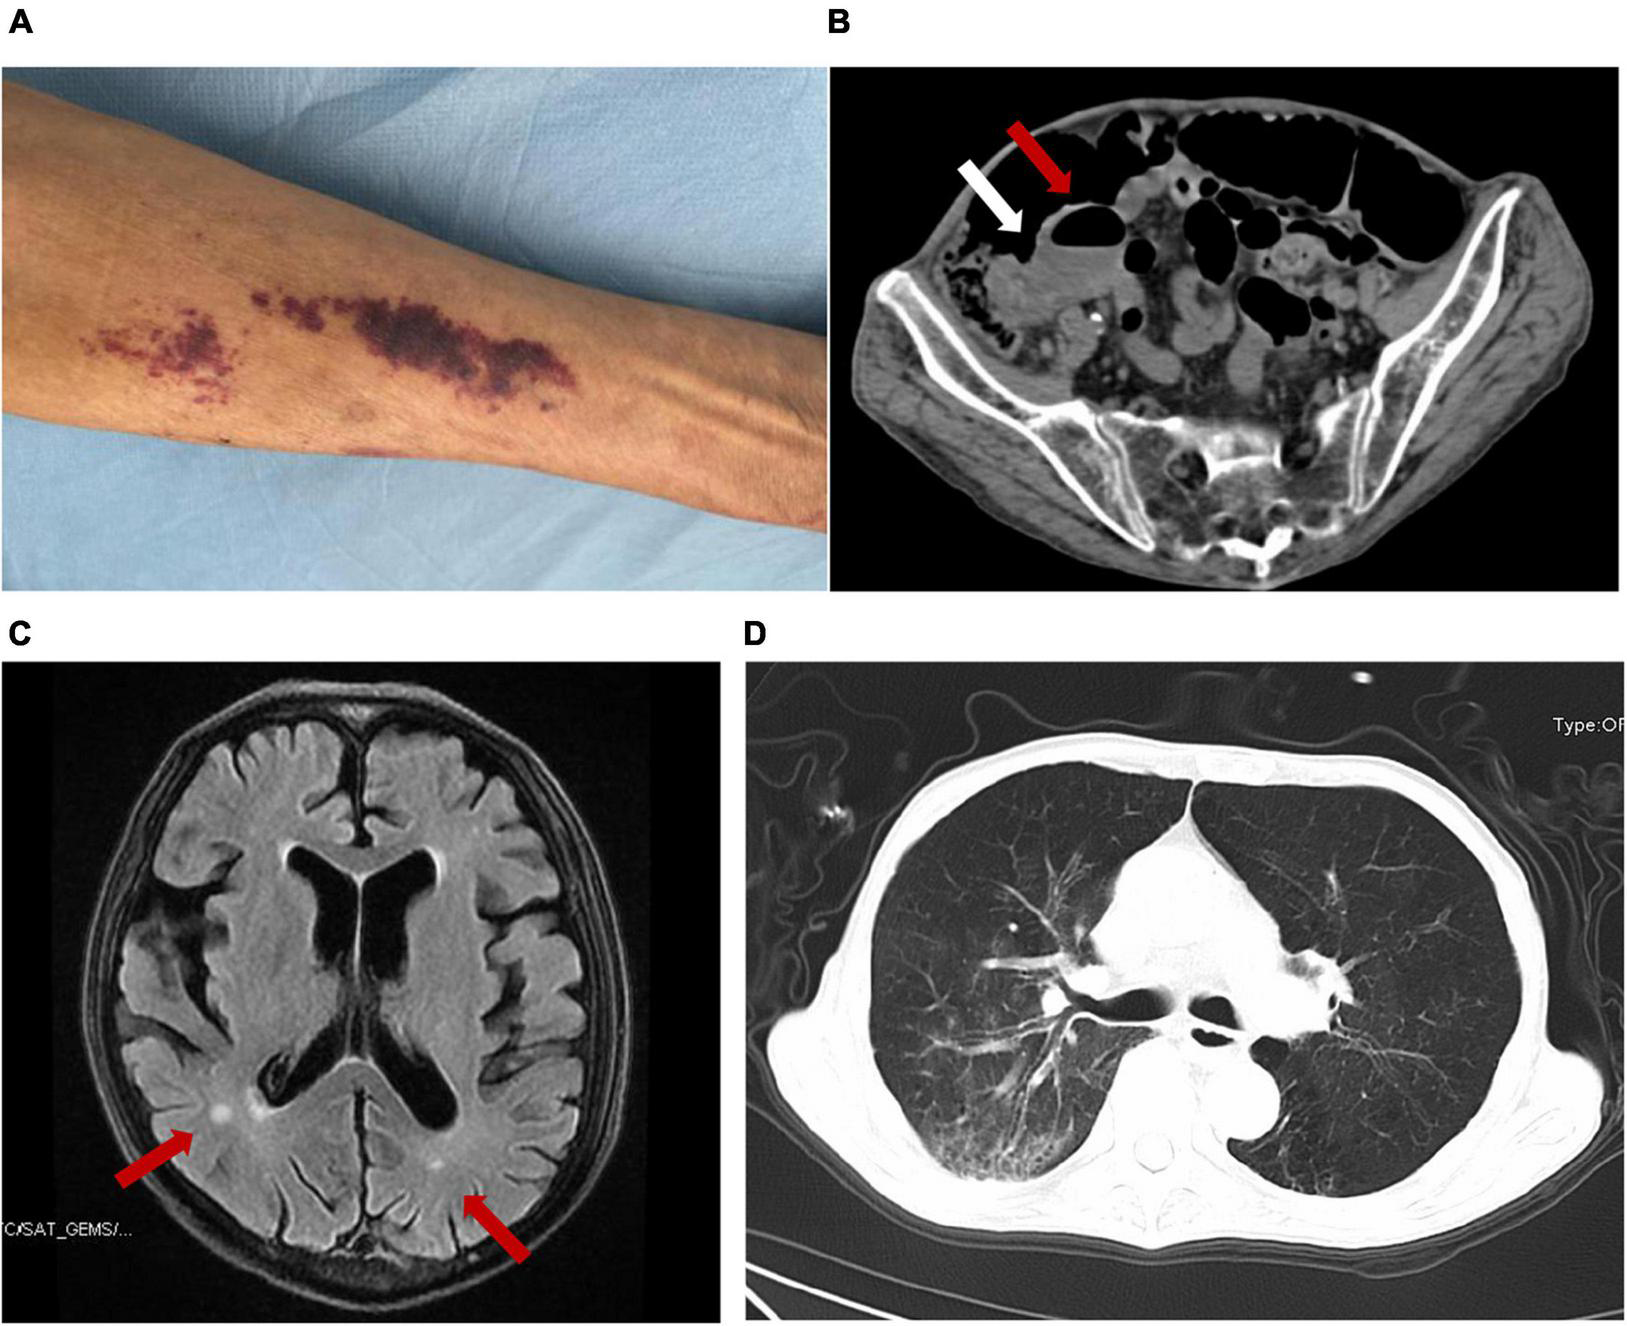

A 67-year-old Chinese male was admitted to our hospital for nearly 2 months of abdominal pain, fever, headache, vomiting, constipation, and slight cough with sputum but without shortness of breath. He is a farmer living on the outskirts of Chengdu, Sichuan Province, southwest China. He had no significant family history, had no underlying diseases, did not use glucocorticoids or immunosuppressive agents, did not drink alcohol, and had not traveled outside Sichuan, a non-endemic area of S. stercoralis. CSF analysis at a local hospital 2 months prior to the admission showed increased white blood cells (WBC, 3,534 cell/μl) and proteins (1.97 g/L) and a positive CSF culture with Enterococcus avium. He was diagnosed with bacterial meningitis and intestinal obstruction there. His condition improved after receiving vancomycin but 2 days prior to the admission he had recurrent, severe vomiting and abdominal pain and therefore was transferred to our hospital for referral. The patient had a 10-kg weight loss in the previous 2 months. On examination, he was afebrile but had neck stiffness. Anaphylactoid purpura were present on both upper limbs (Figure 1A) and facial skin. Signs of meningeal irritation were positive. Crackles were heard bilaterally in the lower lungs on auscultation. Right lower abdominal tenderness and scant bowel sounds were noted. His routine blood work on admission revealed 7.2 × 109/L WBC (normal range, 3.5–9.5 × 109/L) with 86.8% neutrophils, 7.4% lymphocytes and 0% eosinophils, and moderate anemia with 80 g/L hemoglobin. Lymphocyte test showed a decreased CD4+ T cell count of 168 cell/μl (normal range, 471–1,220 cell/μl), CD8+ T cell count of 149 cell/μl (normal range, 303–1,003 cell/μl), B cell count of 24 cell/μl (normal range, 175–332 cell/μl), and normal NK cell of 162 cell/μl (normal range, 154–768 cell/μl). Serum tests for human immunodeficiency virus (HIV), hepatitis B virus (HBV), hepatitis C virus (HCV) and syphilis were negative. PCR testing of a blood sample for human T lymphocyte virus 1 (HTLV-1) was also negative. In blood chemistry, bilirubins, alanine and aspartate aminotransferases, creatine, and urea were all in the normal range. Enhanced brain magnetic resonance imaging (MRI) showed a few patches near bilateral ventricles and partial thickening and strengthening of the endocranium (Figure 1B). An enhanced abdominal computer tomography (CT) scan exhibited proximal small intestinal obstruction (Figure 1C). A CT scan of the chest revealed bronchiectasis with secondary pulmonary infection (Figure 1D). Lumbar puncture on admission revealed clear CSF with 20 red blood cells and 18 WBC per microliter. Meningitis was diagnosed and meropenem was given at 2 g every 8 h for empirical therapy. Small bowel obstruction management measures including gastrointestinal decompression and fluid resuscitation were also given.

FIGURE 1

The presentation of this case and the detection of S. stercoralis larvae. Anaphylactoid purpura were present on left upper limb (A). Abdominal CT imaging showed that the ileocecum was swollen and thickened (white arrow) and the proximal small intestine was obstructed with air-fluid level (red arrow) (B). Brain MRI showed patches near bilateral ventricles (red arrow) and partial endocranium thickened (C). Chest CT revealed bronchiectasis with secondary pulmonary infection (D).